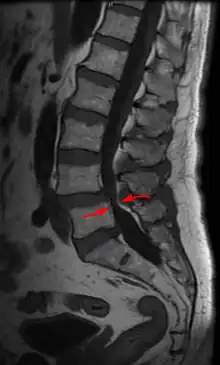

Lumbar vertebra showing central stenosis and lateral recess stenosis. | |

Spinal stenosis may be congenital (rarely) or acquired (degenerative), overlapping changes normally seen in the aging spine.[6][7] Stenosis can occur as either central stenosis (the narrowing of the entire canal) or foraminal stenosis (the narrowing of the foramen through which the nerve root exits the spinal canal). Severe narrowing of the lateral portion of the canal is called lateral recess stenosis. The ligamentum flavum (yellow ligament), an important structural component intimately adjacent to the posterior portion of the dural sac (nerve sac) can become thickened and cause stenosis. The articular facets, also in the posterior portion of the bony spine can become thickened and enlarged, causing stenosis. These changes are often called "trophic changes" or "facet trophism" in radiology reports. As the canal becomes smaller, resembling a triangular shape, it is called a "trefoil" canal.